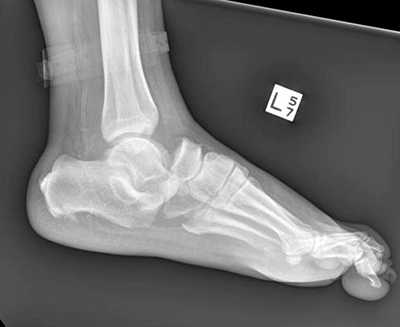

Рентгенография используется для определения угла между линиями, проведёнными между первой плюсневой костью и проксимальной фалангой первого пальца. Если угол больше 15°, подтверждает диагноз hallux valgus. Если угол составляет 45-50° — консервативное лечение не показано. Также должны быть определены степень смещения сесамовидных костей и уровень остеоартрита первого плюсне-фалангового сустава.

Тестирование пациента должно осуществляться два раза: в положении сидя и стоя. В положении стоя деформация стопы наиболее выражена. Во время исследования также необходимо обратить внимание на плоскостопие и степень натяжения ахиллова сухожилия, высоту продольного свода и положение большого пальца по отношению к остальным.

Если неоперативное лечение не помогло, необходимо рассмотреть вопрос о хирургическом лечении (уровень доказательности: 4). Перед выполнением операции необходимо определить степень тяжести hallux valgus. Для этого следует выполнить рентгенографию стоп в положении стоя.